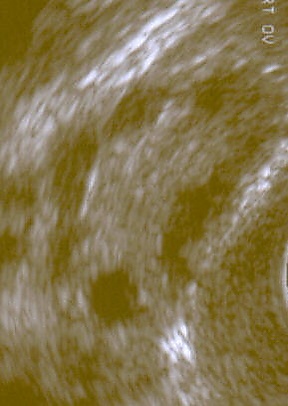

- Множественные кисты яичников. Сонографически они могут выглядеть как «жемчужное ожерелье», скопление белёсых пузырьков или «косточки фрукта», рассеянные по всей ткани яичников;

- Увеличение размеров яичников в 1,5—3 раза за счёт возникновения множества мелких кист;

- Поликистозные яичники при ультразвуковом исследовании органов малого таза